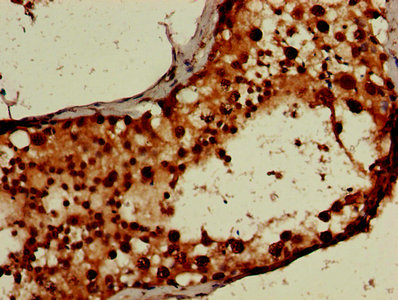

IHC image of CSB-PA897459LA01HU diluted at 1:600 and staining in paraffin-embedded human kidney tissue performed on a Leica BondTM system. After dewaxing and hydration, antigen retrieval was mediated by high pressure in a citrate buffer (pH 6.0). Section was blocked with 10% normal goat serum 30min at RT. Then primary antibody (1% BSA) was incubated at 4°C overnight. The primary is detected by a biotinylated secondary antibody and visualized using an HRP conjugated SP system.

IHC image of CSB-PA897459LA01HU diluted at 1:600 and staining in paraffin-embedded human testis tissue performed on a Leica BondTM system. After dewaxing and hydration, antigen retrieval was mediated by high pressure in a citrate buffer (pH 6.0). Section was blocked with 10% normal goat serum 30min at RT. Then primary antibody (1% BSA) was incubated at 4°C overnight. The primary is detected by a biotinylated secondary antibody and visualized using an HRP conjugated SP system.